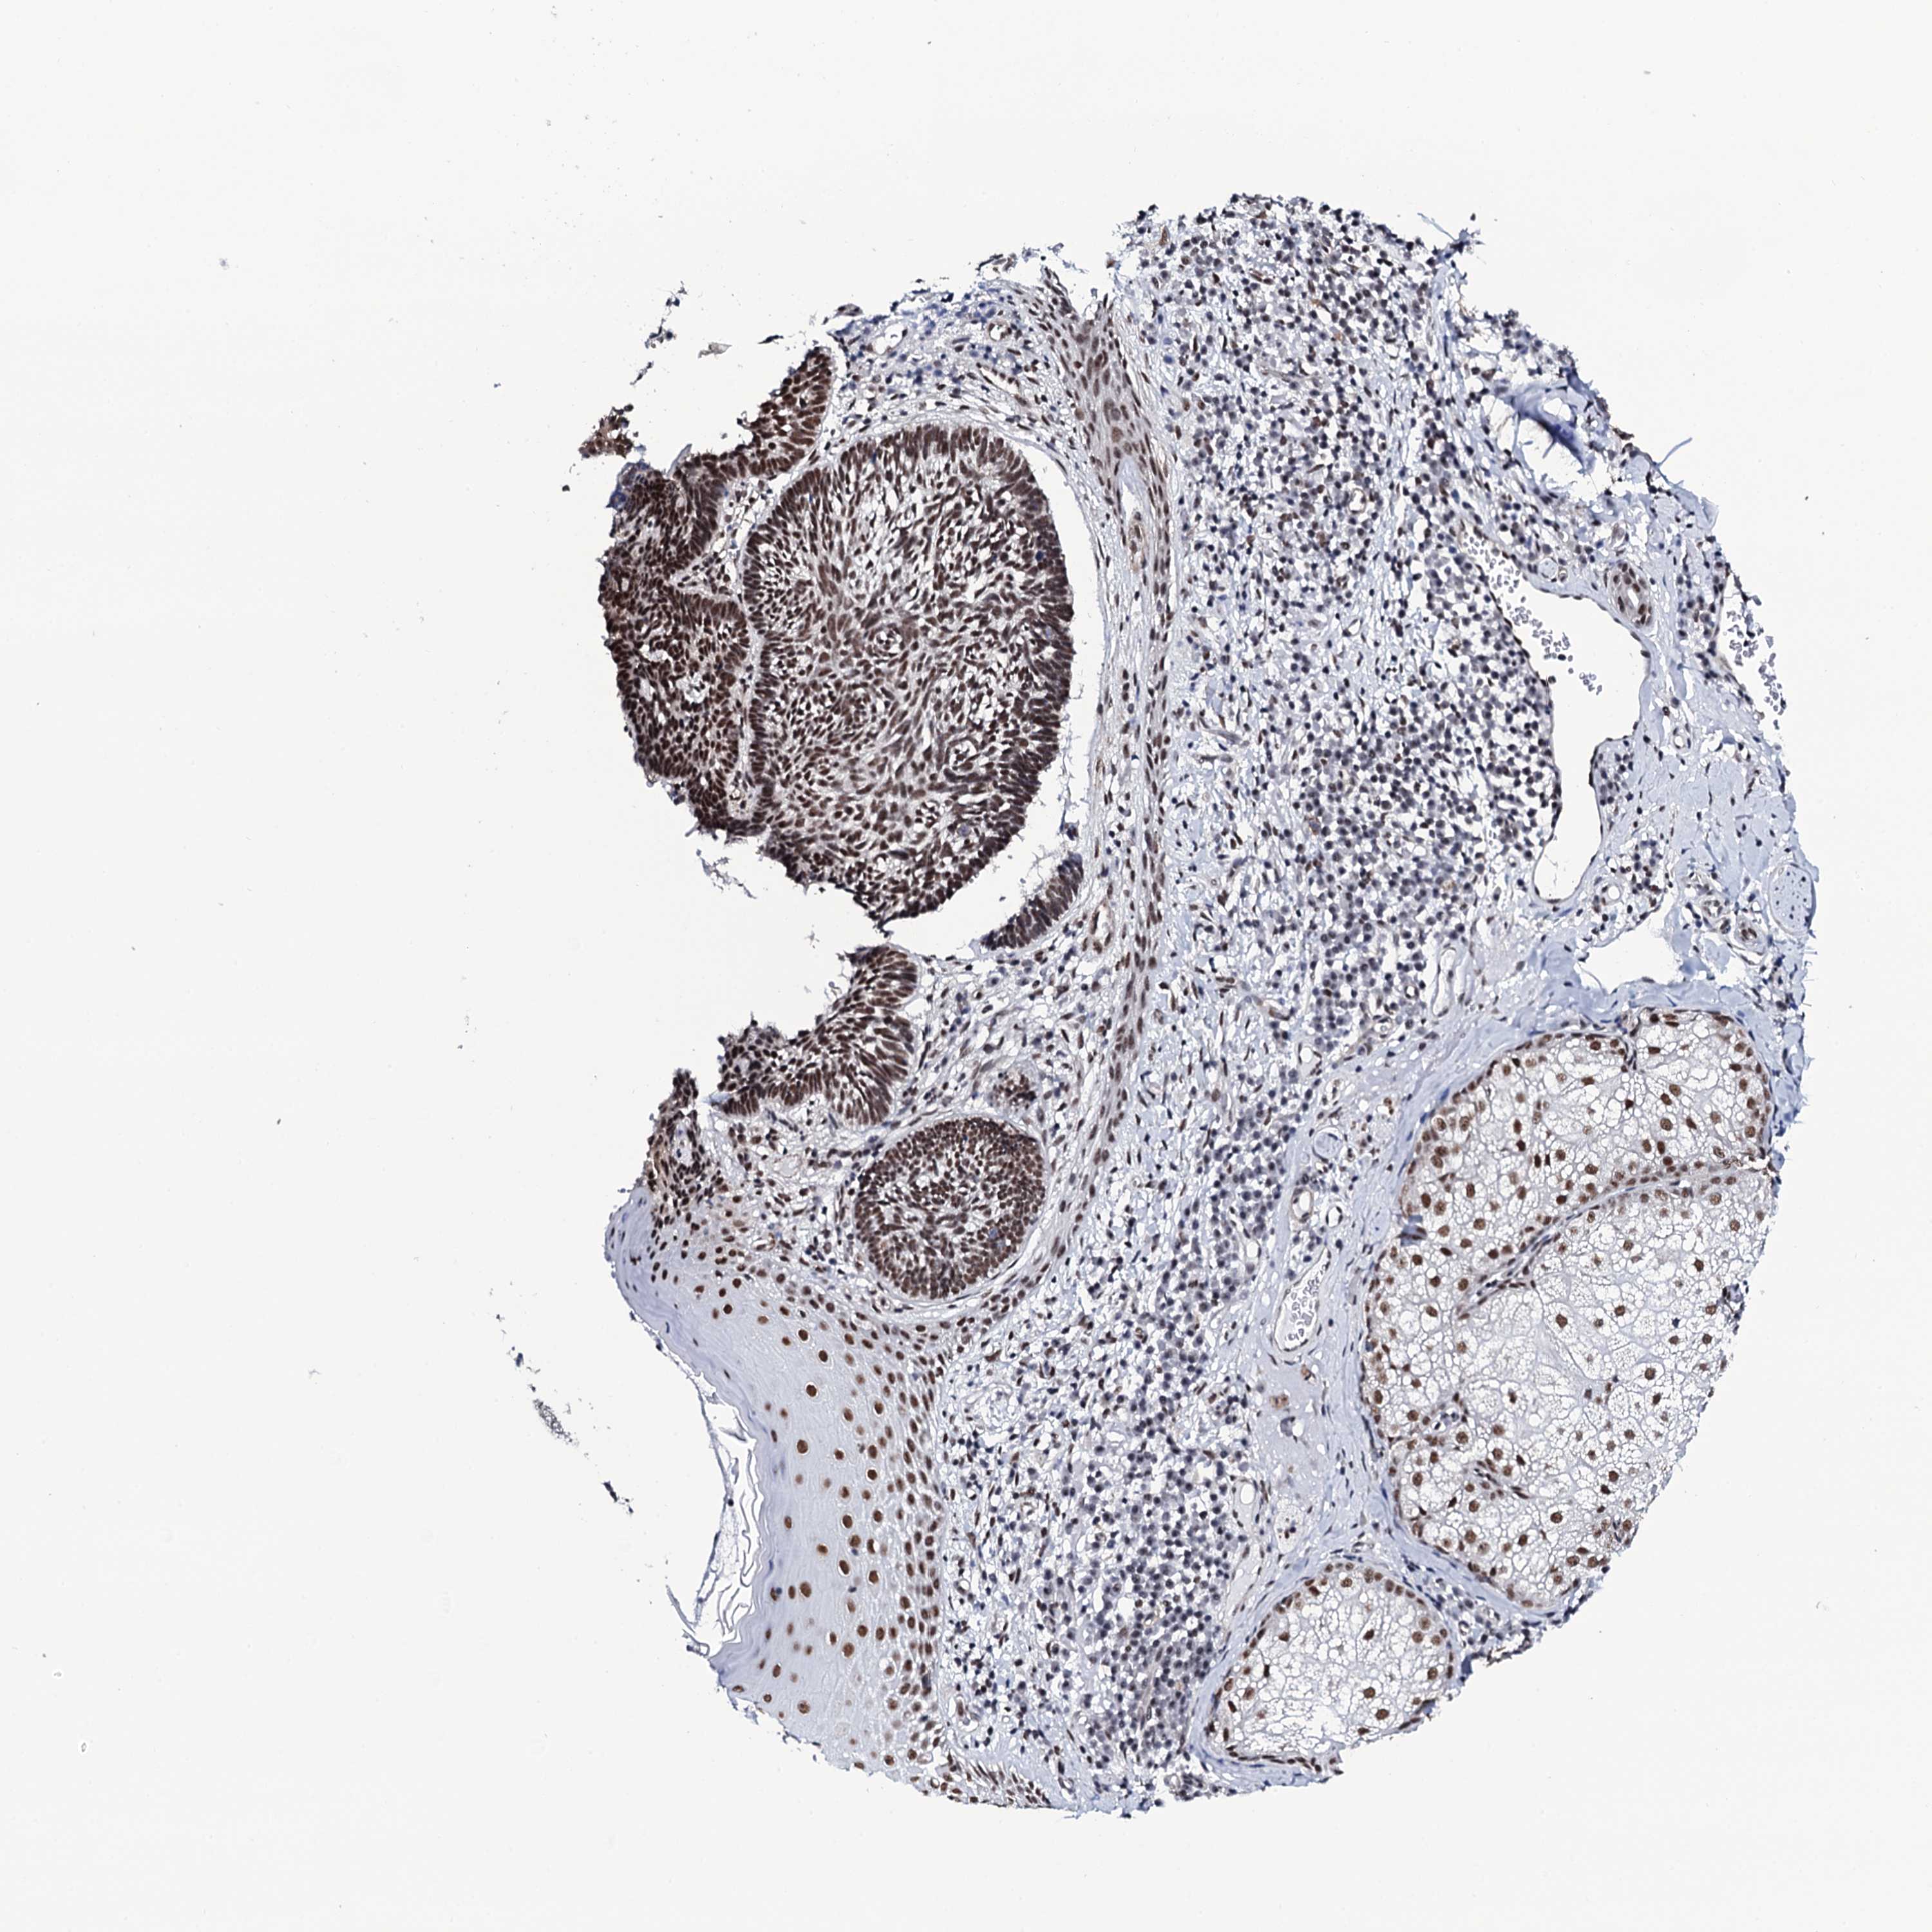

Basal cell and squamous cell cancer

SKIN CANCER - Protein expressioni

A mouse-over function shows sample information and annotation data. Click on an image to view it in a full screen mode. Samples can be filtered based on level of antibody staining by selecting one or several of the following categories: high, medium, low and not detected. The assay and annotation is described here.

Antibody stainingi

Antibody staining in the annotated cell types in the current human tissue is reported as not detected, low, medium, or high, based on conventional immunohistochemistry profiling in selected tissues. This score is based on the combination of the staining intensity and fraction of stained cells.

Each image is clickable and will lead to virtual microscopy that enables deeper exploration of all samples and also displays staining intensity scores, fraction scores and subcellular localization as well as patient and tissue information for each sample.

Antibody HPA039878

Staining

High

Medium

Low

Not detected

Intensity

Strong

Moderate

Weak

Negative

Quantity

>75%

75%-25%

<25%

None

Location

Nuclear

Cytoplasmic/membranous

Cytoplasmic/membranous,nuclear

Basal cell carcinoma